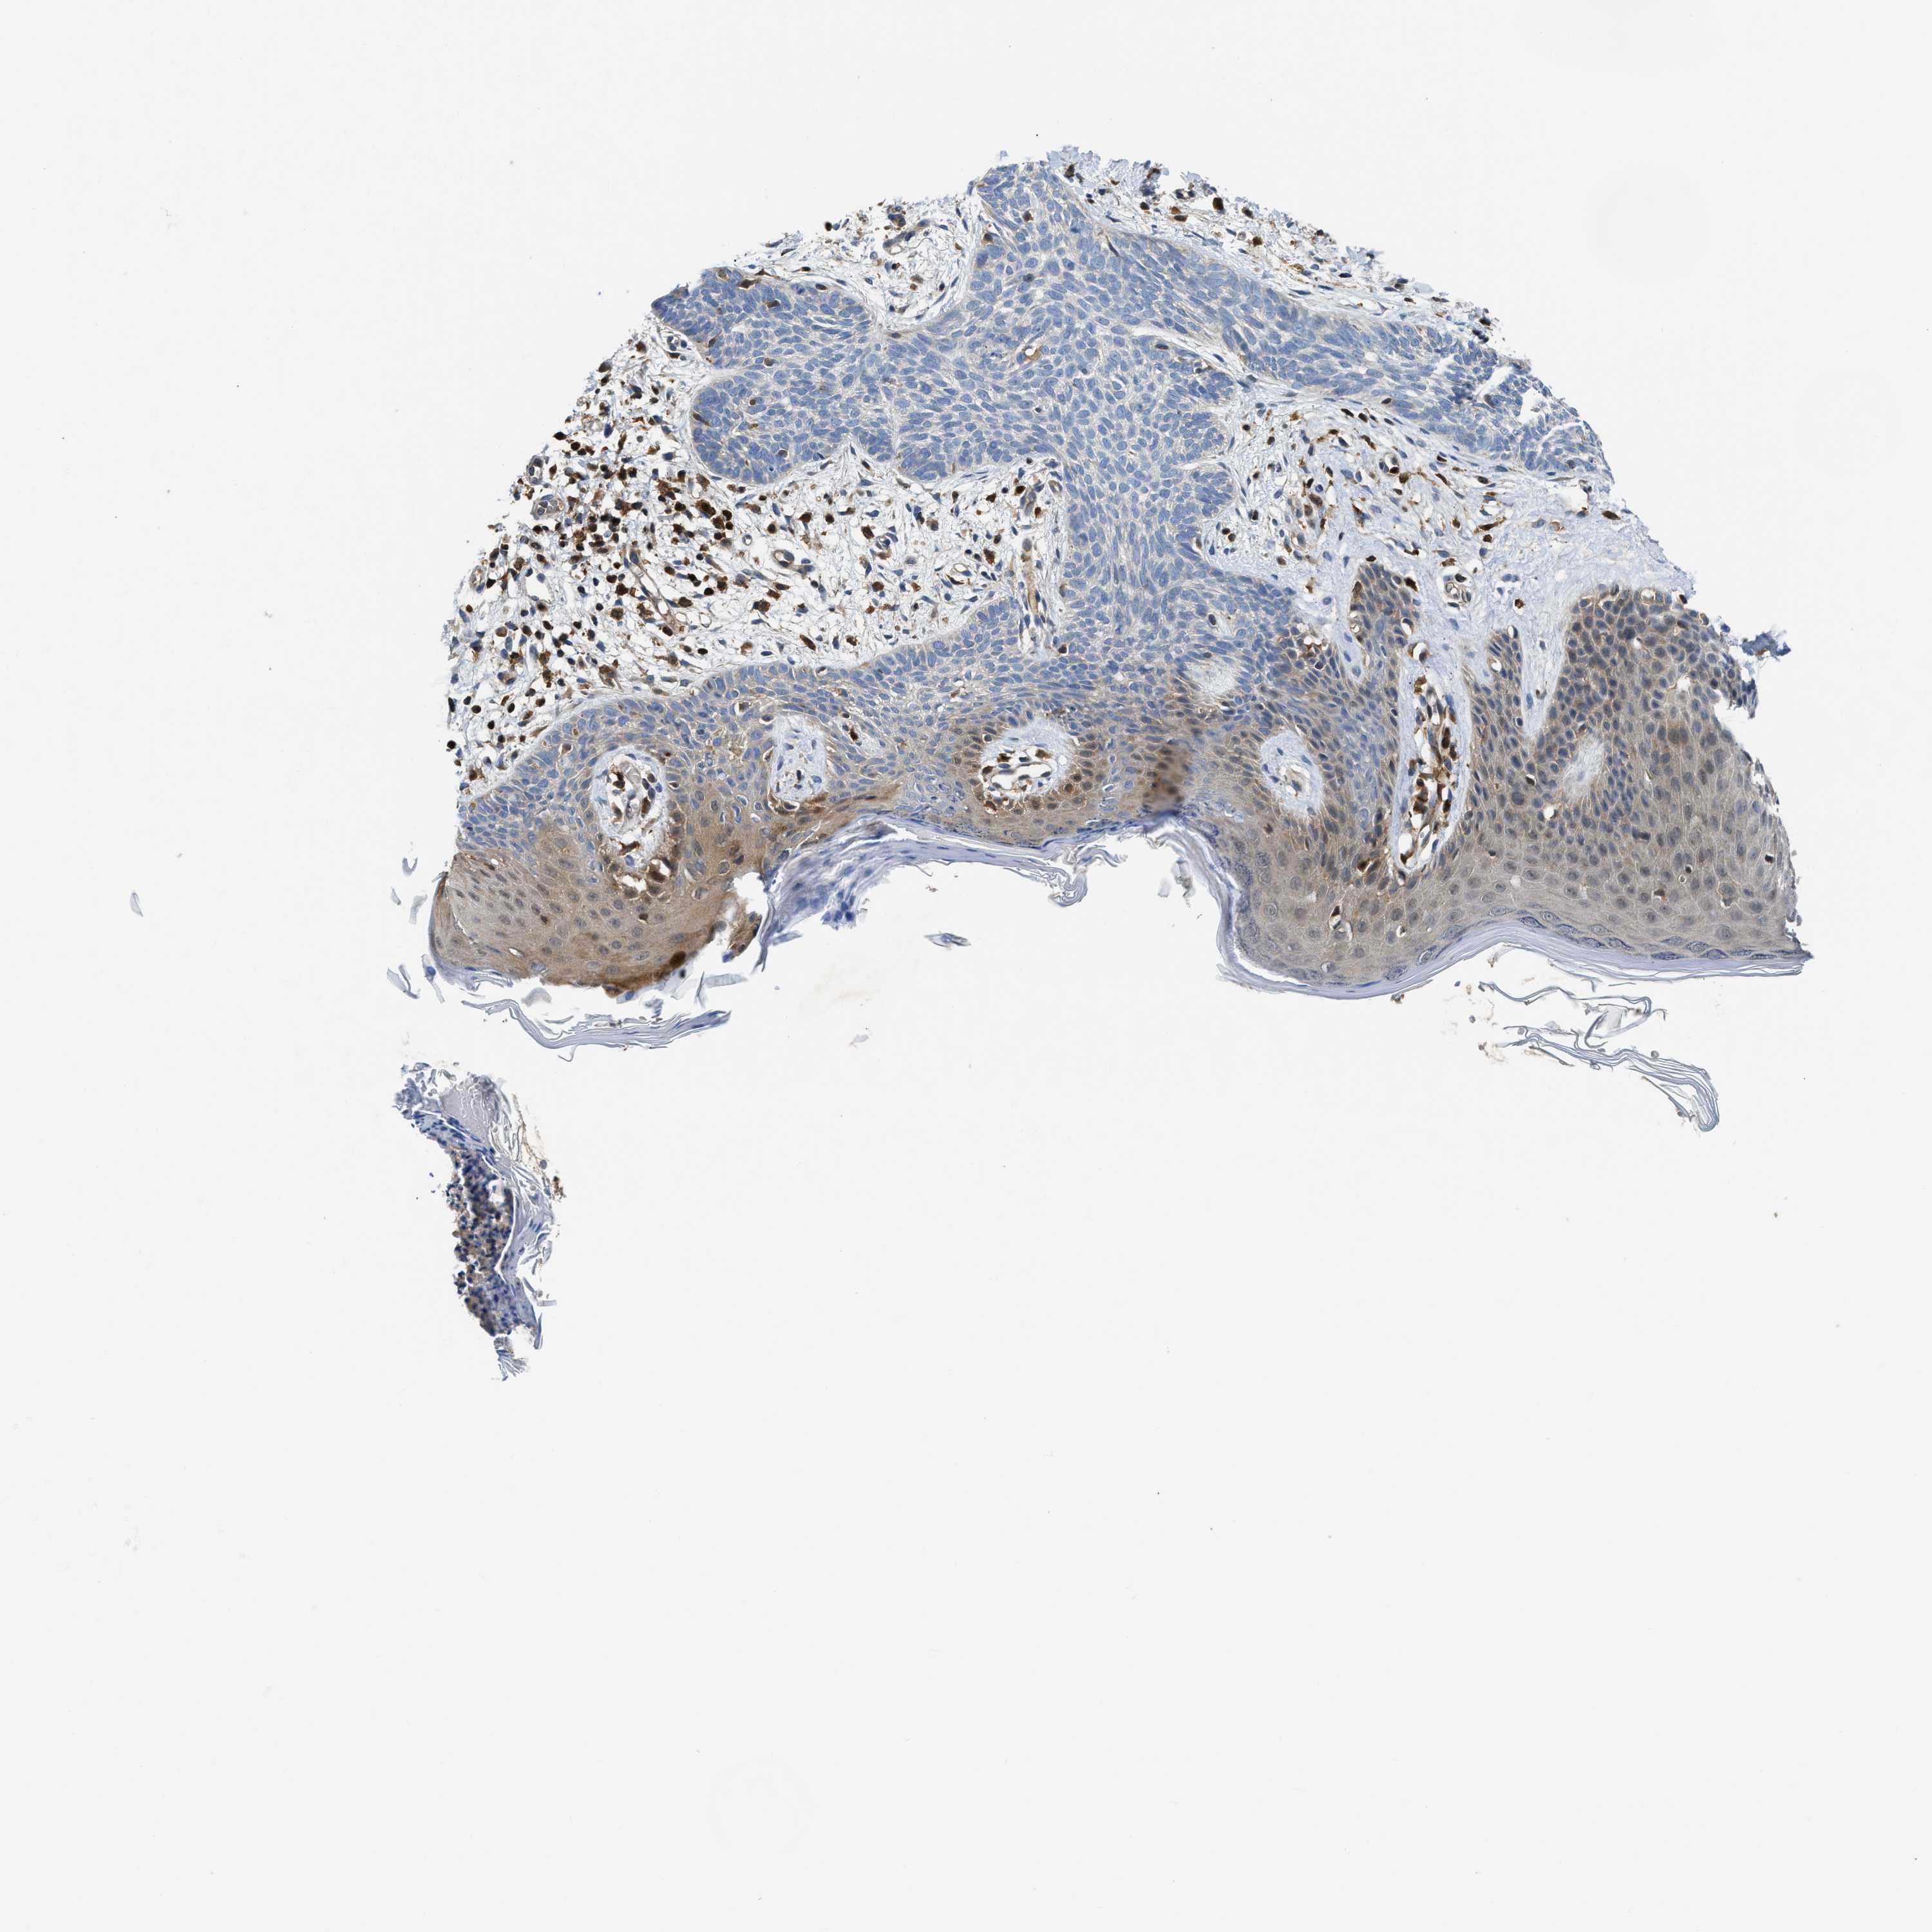

SKIN CANCER - Protein expressioni

A mouse-over function shows sample information and annotation data. Click on an image to view it in a full screen mode. Samples can be filtered based on level of antibody staining by selecting one or several of the following categories: high, medium, low and not detected. The assay and annotation is described here.

Antibody stainingi

Antibody staining in the annotated cell types in the current human tissue is reported as not detected, low, medium, or high, based on conventional immunohistochemistry profiling in selected tissues. This score is based on the combination of the staining intensity and fraction of stained cells.

Each image is clickable and will lead to virtual microscopy that enables deeper exploration of all samples and also displays staining intensity scores, fraction scores and subcellular localization as well as patient and tissue information for each sample.

Antibody HPA020514

Staining

High

Medium

Low

Not detected

Intensity

Strong

Moderate

Weak

Negative

Quantity

>75%

75%-25%

<25%

None

Location

Nuclear

Cytoplasmic/membranous

Cytoplasmic/membranous,nuclear

Squamous cell carcinoma in situ, NOS